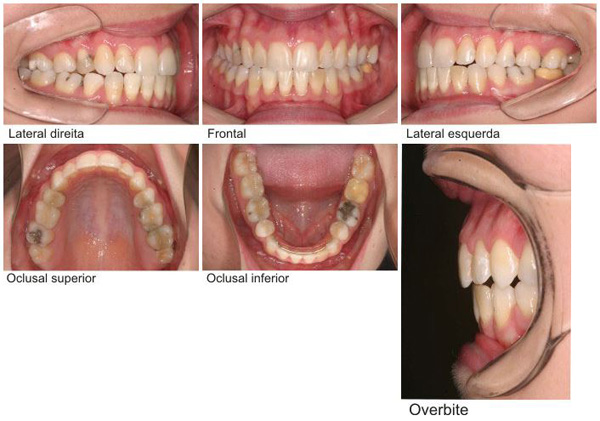

• PAINEL DE FOTOS

DOCUMENTAÇÃO STANDE R COM OCLUSAL

• PAINEL DE FOTOS DOCUMENTAÇÃO ORTODONTICA COMPLETA